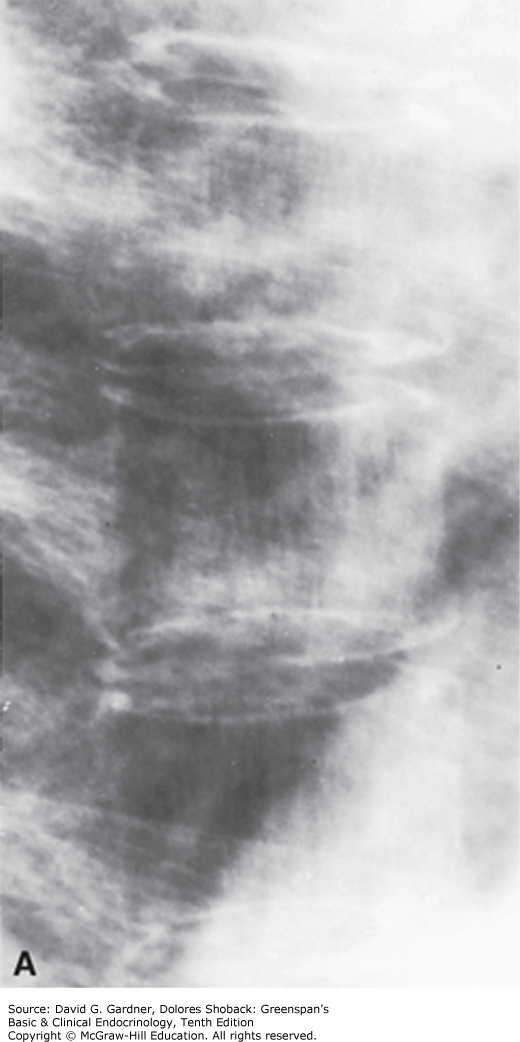

A. Magnified x-rays of thoracic vertebrae from a woman with osteoporosis. Note the relative prominence of vertical trabeculae and the absence of horizontal trabeculae. B. Lateral x-ray of the lumbar spine of a woman with postmenopausal osteoporosis. Note the increased density of the superior and inferior cortical margins of vertebrae, the marked demineralization of vertebral bodies, and the central compression of articular surfaces of vertebral bodies by intervertebral disks. (Used with permission from Dr. G. Gordan.)